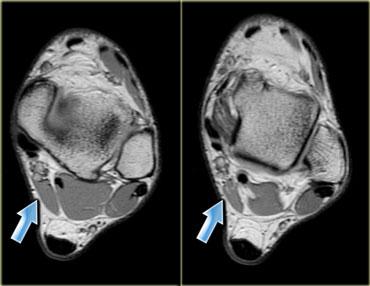

Hình bên trái là một ví dụ khác về cơ phụ nằm ở phía trong so với cơ gấp ngón cái dài (ở giữa) và cơ mác ngắn (ở ngoài).

Đây là vị trí thường gặp của các cơ phụ, và có nhiều loại cơ khác nhau có thể xuất hiện tại đây (để phân biệt cần xác định vị trí bám của gân).

Lý do bệnh nhân được chỉ định chẩn đoán hình ảnh là vì cơ phụ này chèn ép bó mạch thần kinh lân cận, dẫn đến teo cơ bàn chân hoặc hội chứng ống cổ chân với cảm giác tê bì lòng bàn chân hay yếu cơ.